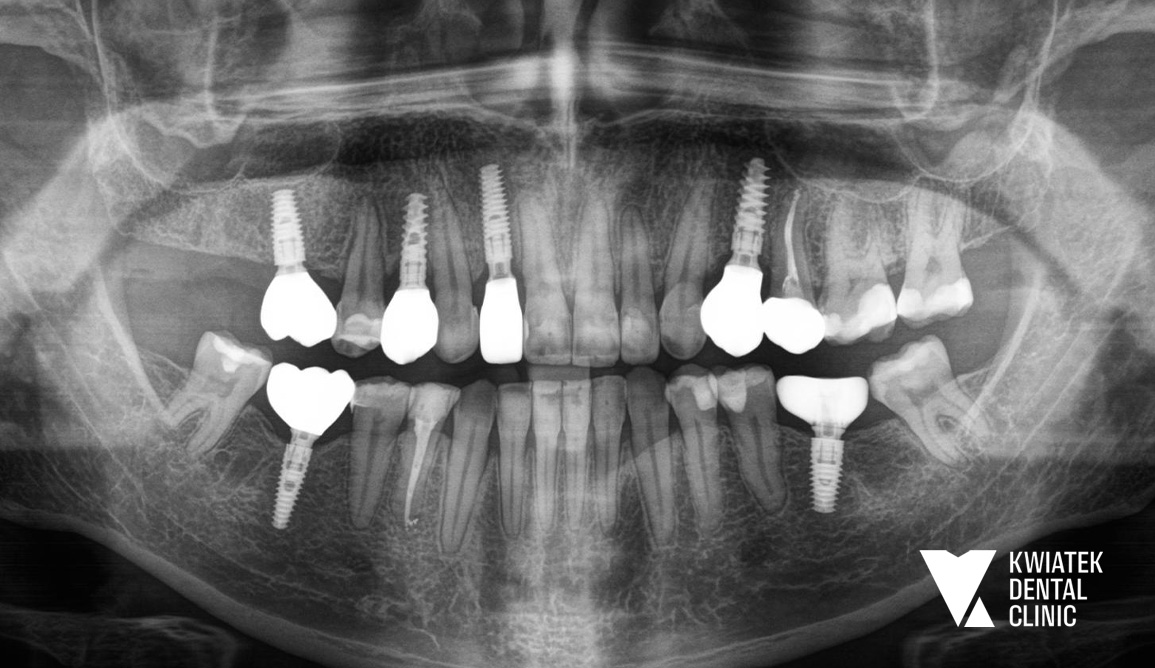

Rozpoczęto od zabiegów chirurgicznych i usunięcia zębów niekwalifikujących się do leczenia. Następnie wdrożono zaawansowane procedury implantologiczne, w tym natychmiastowe implantacje oraz zabiegi augmentacji kości z użyciem biomateriałów.

W przypadku zęba 24 konieczne było ponowne podejście implantologiczne po braku integracji, które zakończyło się powodzeniem. W odcinku przednim zastosowano nowoczesne techniki implantacji natychmiastowej, zapewniające zachowanie estetyki już na etapie leczenia.

Efektem wieloletniej współpracy jest:

To metamorfoza, która nie wydarzyła się w jeden dzień. To historia uśmiechu tworzona wspólnie przez lata, w oparciu o potrzeby Pacjenta i indywidualnie dopasowane rozwiązania terapeutyczne. Nasi specjaliści wspólnie z Pacjentem tworzyli plany leczenia, a ich efekty dziś spotykają się w jednym miejscu podczas wizyt kontrolnych, które są naturalną kontynuacją tej relacji opartej na szacunku i wzajemnym zaufaniu.